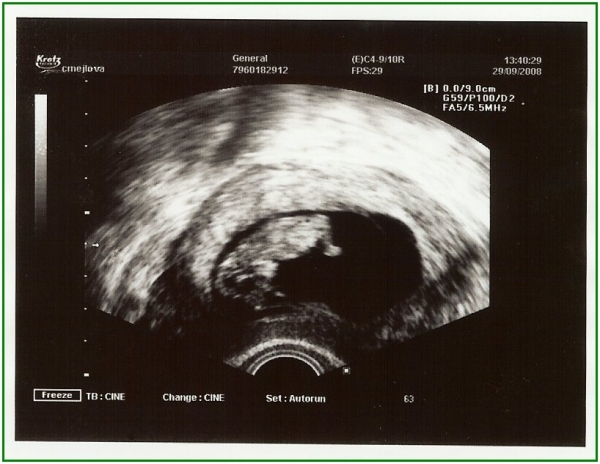

Vajco